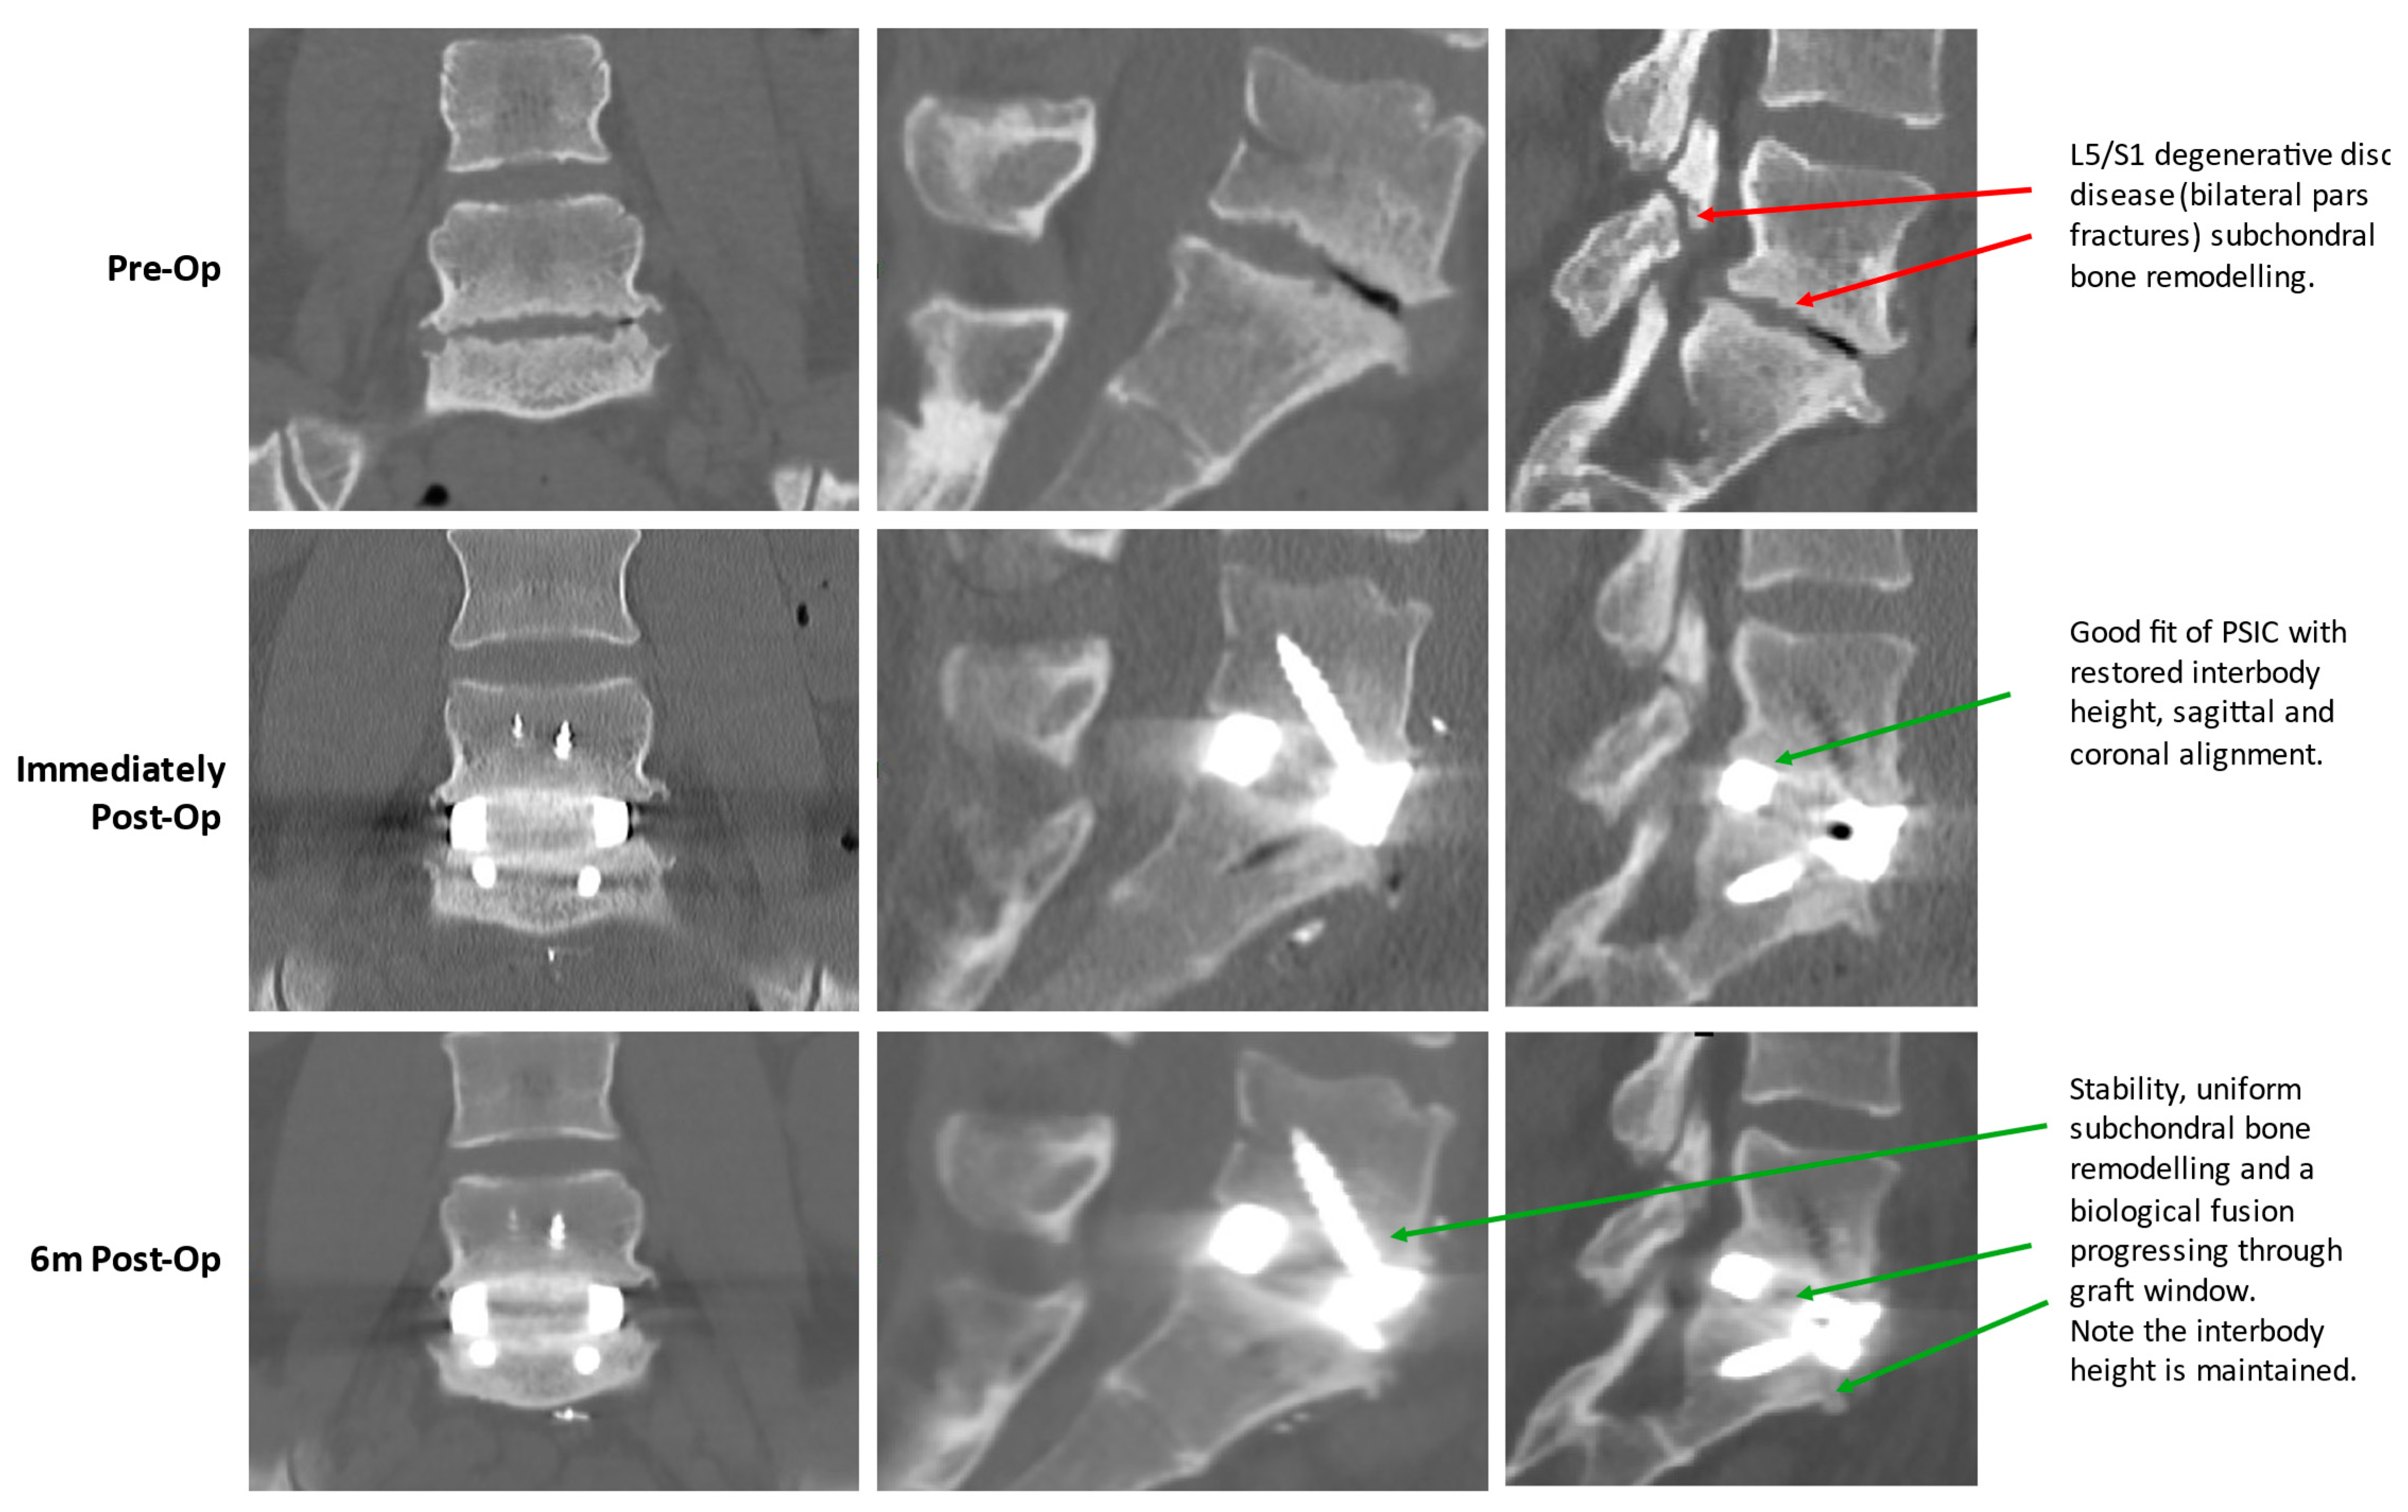

2.1.6. Operative Technique